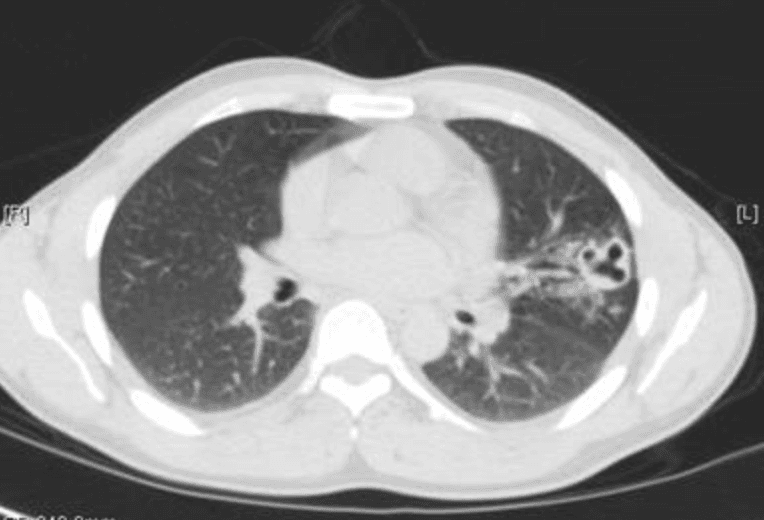

Examination shows mild tachycardia and scattered crackles. Chest imaging revealed a left patchy upper-lobe infiltrates with a small cavitary lesion. Labs show WBC 9,800 cells/uL with eosinophils 8% (absolute eosinophil count 780 cells/uL). Initial AFB sputum smear is negative, MTB PCR is negative, and routine bacterial sputum cultures are negative.

CT chest without contrast.